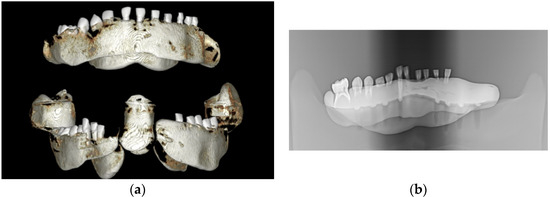

3.1. Scanning Electron Microscopy (SEM)